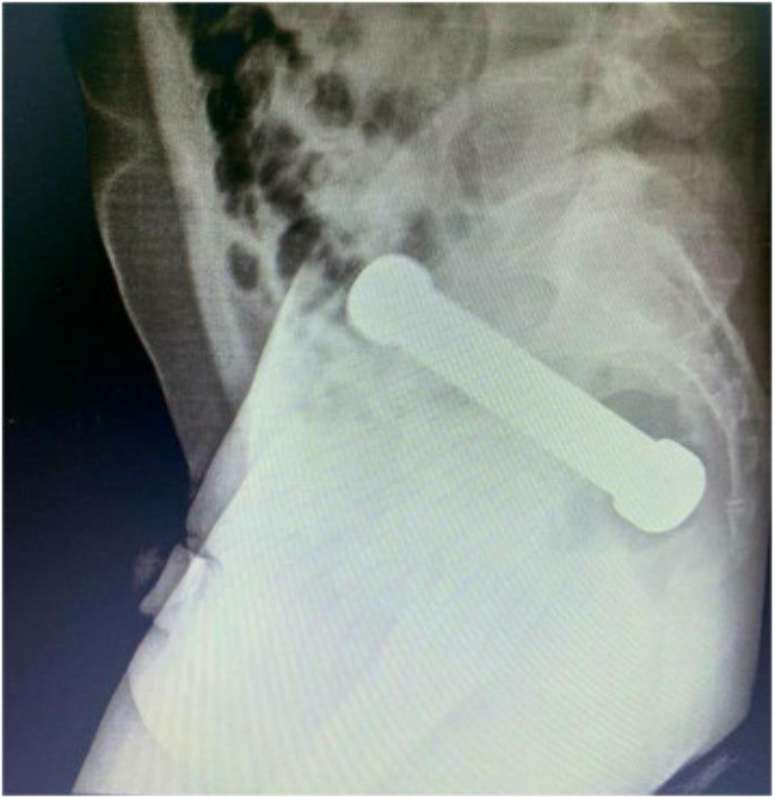

Foto: International Journal of Surgery Case Reports

Os médicos solicitaram exames para descobrir a origem do problema e se surpreenderam com as imagens de radiografia, que revelaram um halter, aquele peso de mão usado em academias, dentro do corpo do paciente.

O objeto tinha 20 centímetros e dois quilos. Foi necessário um procedimento cirúrgico para anestesiar o homem e poder retirar o halter de seu corpo. A cirurgia foi bem sucedida e o paciente recebeu alta após três dias internado.

O episódio foi descrito na International Journal of Surgery Case Reports com o título ”manejo de incomum corpo estranho retal” e com algumas fotos para ilustrar a excepcionalidade do caso.